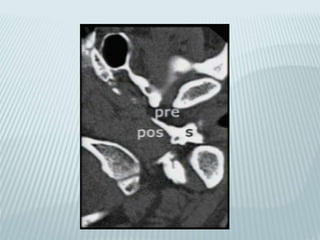

CT PROTOCOL

 Axial supine 1mm

 Coronal Prone 1mm

 120 kv@200mA :1sec

 512x512 @140mmFOV